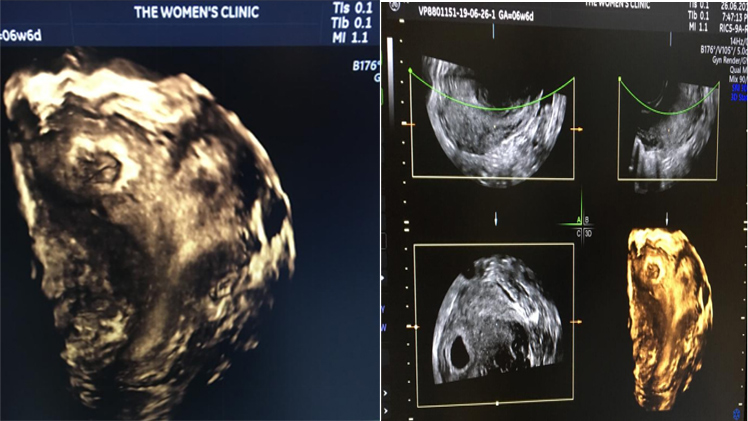

Case 1

A 28 yrs old female with 2 abortions (recurrent abortion) in the past was anxious to conceive.

• 1st abortion at 4 months of pregnancy

• 2nd abortion at 5 months of pregnancy

• This time she was pregnant and had come to us seeking help to maintain current pregnancy.

• We went ahead and did a 3D ultrasound for her on our advanced GE Voluson P8 machine.

• 3D Ultrasound for her showed a uterus with a minor birth defect and thereafter her pregnancy was managed accordingly. She now has a baby boy!